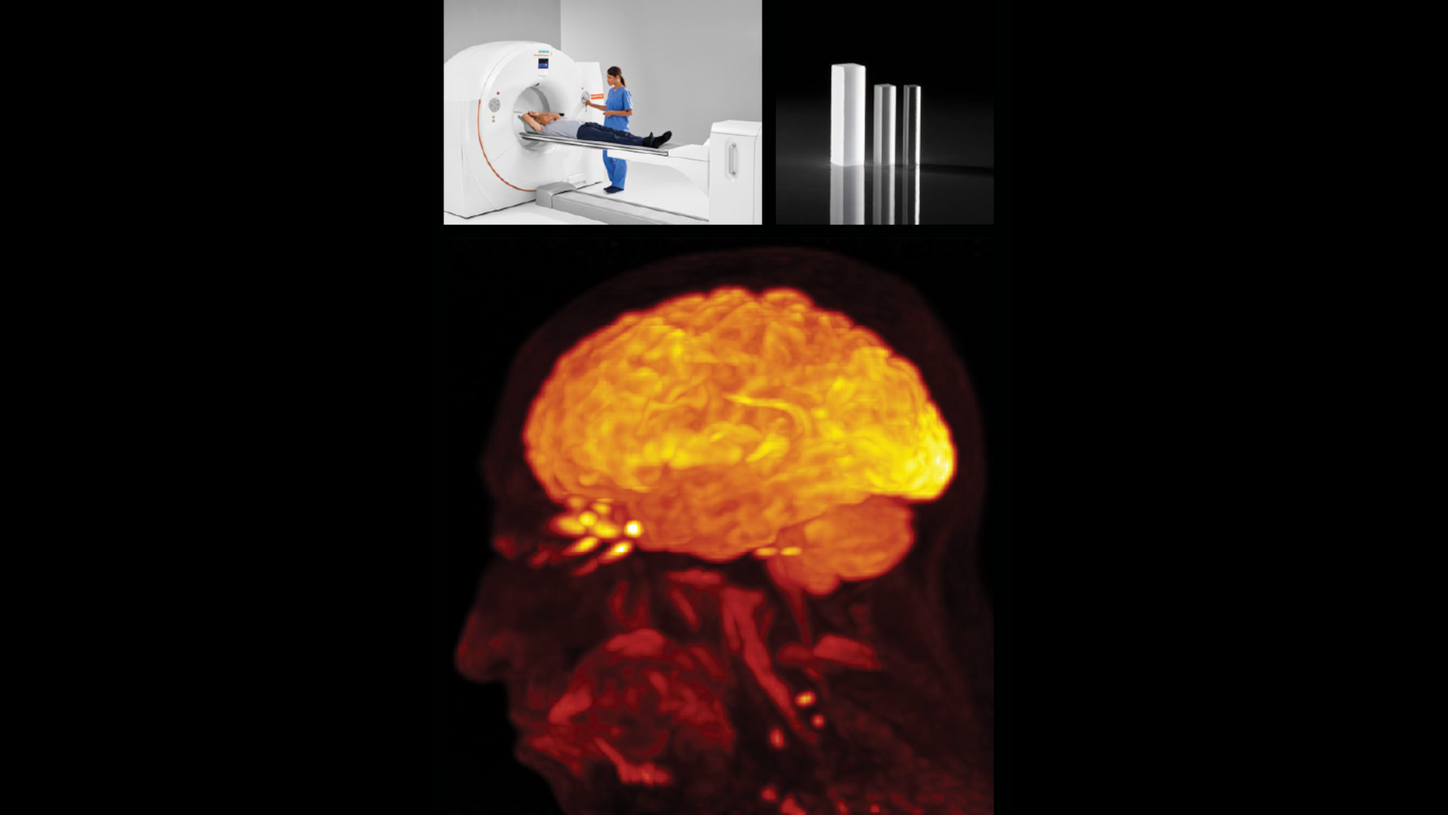

Pushing PET/CT forward with ground-breaking innovation

Since PET/CT’s unveiling at RSNA, the modality’s capabilities continue to expand. Maurizio Conti, PhD, joined the Siemens molecular imaging team in 2000. Today, he serves as director of PET Physics and Reconstruction at Siemens Healthineers in Knoxville. When asked about the biggest technological developments in PET/CT over the past 25 years, he quickly points to two key milestones: replacing BGO detector blocks with lutetium oxyorthosilicate (LSO) scintillators, which enabled time-of-flight (TOF) imaging, and the later introduction of silicon photomultipliers (SiPMs), which dramatically improved time resolution. These two breakthroughs significantly elevated image quality and greatly accelerated the scanning time, which in turn helped increase patient comfort.

Conti also speaks with particular pride about two projects: the first TOF PET/CT scanner from Siemens Healthineers, Biograph mCT, which was “a revolution in those years—a truly outstanding machine,” he says— and Biograph Vision Quadra total-body PET/CT. “It was an unusually fast project. Can you believe that it was done in about 1.5 years?”

2017

Biograph Vision PET/CT is launched with an innovative design that reduces the size of the detector’s crystal elements from 4 x 4 mm to 3.2 x 3.2 mm and generates 214-picosecondtrue TOF performance that leverages the full potential of SiPM technology.

Ability to understand disease and improve treatment

The defining strength of PET/CT remains its ability to combine functionality and anatomy in a single scan. But there is even more to it today. “Using different tracers, and more specific tracers, we can understand not only what a disease is, but if it’s aggressive or not. And that correlates with the organs and the anatomy, which only PET/CT can do,” Conti explains.

It all started with the generic tracer fludeoxyglucose injection F 18 (FDG) to measure metabolism. But now, a growing number of novel tracers are available, providing deeper insight into disease function that comes with PET. “This is a great future,” says Conti. “Today, we have access to highly specific tracers such as PSMA for prostate cancer, tau and amyloid for dementia and Alzheimer’s disease evaluation, and rubidium for cardiac imaging. As the spectrum tracers broadens, so does the potential for earlier, more accurate disease detection and improved treatment monitoring.”